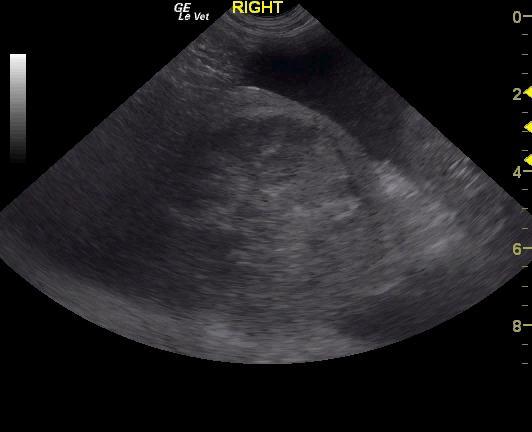

The spleen contained a mixed, echogenic complex mass that measured 10+ cm. The mass was deriving from the caudal splenic body. A large amount of free fluid was noted in the abdomen. Omental nodular changes were noted.

Splenic mass. Free fluid and omental nodular changes. Given that the patient is not overtly anemic, the abdominal fluid is likely paraneoplastic in nature. There was no obvious organ metastasis noted. However, some omental nodular changes could be consistent with seeding.